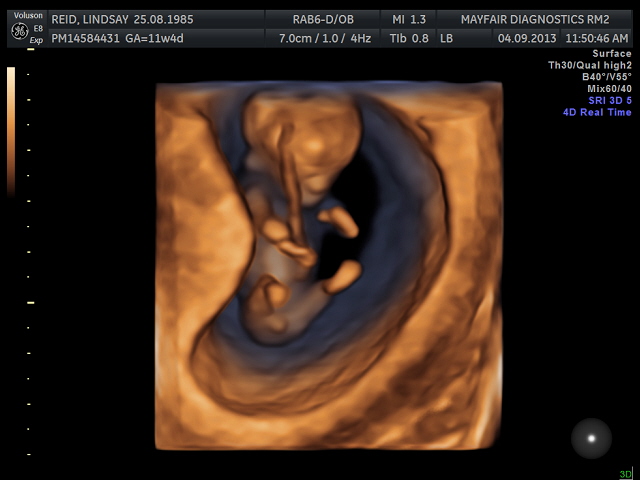

Had my 12 week scan today, I don't have any 2-d nub pics but I do have some 3-d ones! Based on the 3-d nubs and forehead/chin shape, I am guessing boy. :) Was hoping for a girl, but that's okay, lol. Heart rate was 166, baby was hyper and moving around so much!Attachment 13790Attachment 13791Attachment 13789